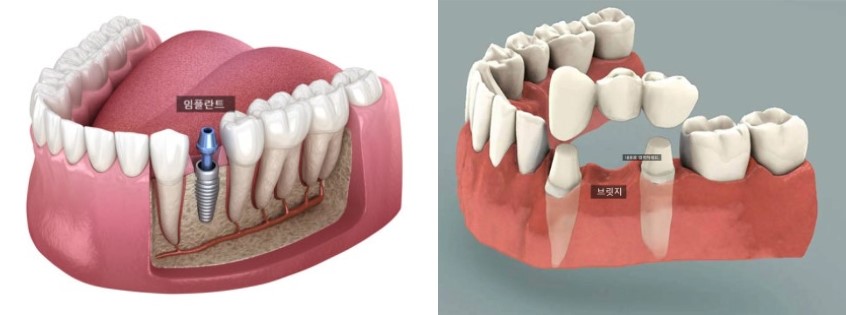

치료 결과

• 결손 부위 공간이 완전히 폐쇄되었습니다.

• 임플란트나 브릿지 없이도 자연스럽고 균형 잡힌 치열로 정리되었습니다.

• 전치부 개방교합이 개선되면서 앞니로 음식물을 자르는 기능이 좋아졌습니다.

• 돌출입도 함께 완화되어 옆모습 인상 역시 부드럽게 변했습니다.

747569ca512315b293293d02a0866f62_1763604888_2302.jpg

보호자와 환자 모두 치료 결과에 매우 만족하셨습니다.